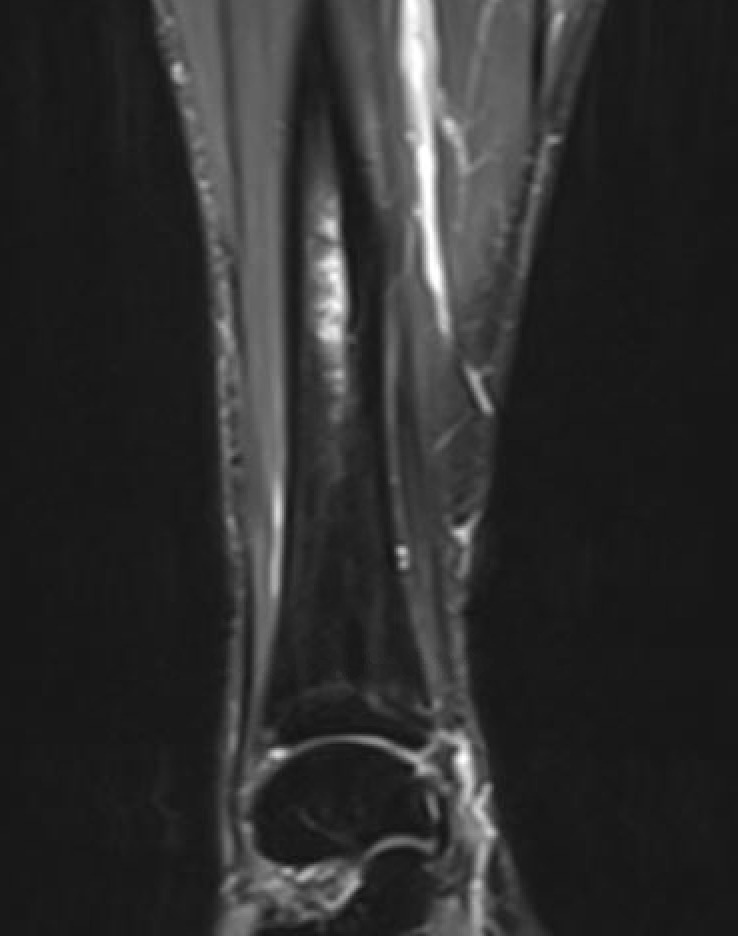

MRI

Fredericson Classification of Medial Tibial Stress Fractures on MRI

Grade 1: Periosteal edema

Grade 2: Bone marrow edema on T2

Grade 3: Bone marrow edema on T1 and T2

Grade 4a: Intra-cortical stress changes

Grade 4b: Frank tibial stress fracture